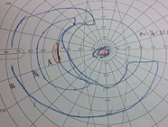

?正常な網膜です。中心部の赤い部分の網膜には、物を見るための視細胞が沢山集まっています。その周りの青にも、視細胞がありますが、赤に比べると数が少なくなります。緑はさらに見え方が落ちる部位です。

?黄斑円孔で、赤の部分の網膜が硝子体に引っ張られて断裂し、無くなってしまうと、視野の中心部が欠損、見たい部分が見えなくなってしまいます。

?手術の効果で、青や緑の網膜を中心部に引き寄せます。

?青の部分の網膜が、視野の中心部の視界を担うようになります。

赤に比べて、青の網膜は、視細胞の数も能力も乏しくなります。この青の網膜が中心部の見え方を担当するようになるので、どんなに回復しても「視力が悪い」、「感度が悪い」、「少し暗く見える」などが残り、完全に元通りという事はあり得ないのです。

青に比べて、緑はさらに感度が悪いのですが、黄斑円孔の穴が大きく、青の部分まで無くなってしまった症例では、緑が中心部の役割を担うために、さらに後遺症が大きく残ります。